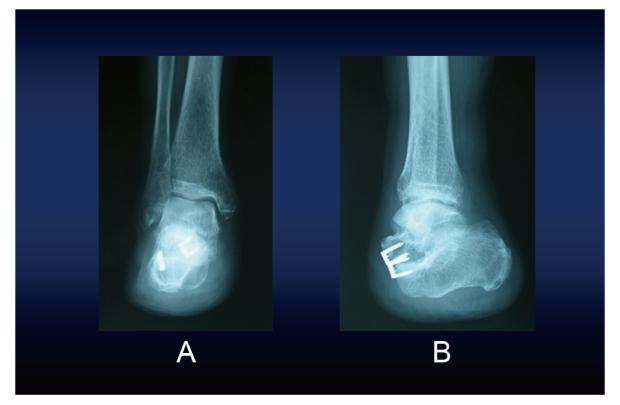

When foot necrosis occurs due to lower limb blood flow disorder caused by diabetes or peripheral arterial occlusion, many patients require lower limb amputation. The functional prognosis after lower limb amputation largely depends on whether the heel can be preserved. However, there are many reports that Chopart amputation causes varus and equinus deformity, and is functionally unfavorable. We herein report a case of Chopart amputation performed with muscle balancing. Postoperatively, the foot was not deformed and the patient was able to walk independently with a foot prosthesis.

A 78-year-old man presented with ischemic necrosis of his right forefoot. The range of necrosis extended to the central part of the sole, so Chopart amputation was performed. In the operation, to prevent varus and equinus deformity, the Achilles tendon was lengthened, the tibialis anterior tendon was transferred through a tunnel created in the neck of talus, and the peroneus brevis tendon was transferred through a tunnel created in the anterior part of the calcaneus. At the final follow-up 7 years after the operation, no varus or equinus deformity was observed. The patient became able to stand up and walk on his heel without a prosthesis. In addition, step motion was possible by wearing a foot prosthesis.